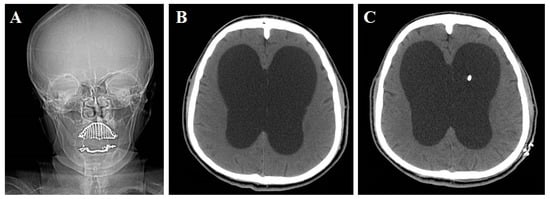

2.2. Image Analysis